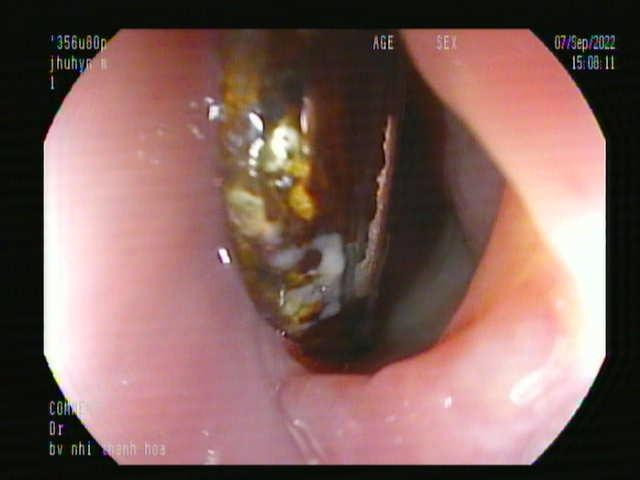

Ngay lập tức, bệnh nhân được kíp nội soi tiêu hóa - gây mê nhanh chóng can thiệp, gắp bỏ được cục pin từ thực quản của bé ra ngoài.

Bệnh nhân N. bị viêm loét thực quản độ 2 do hóa chất trong pin ăn mòn.